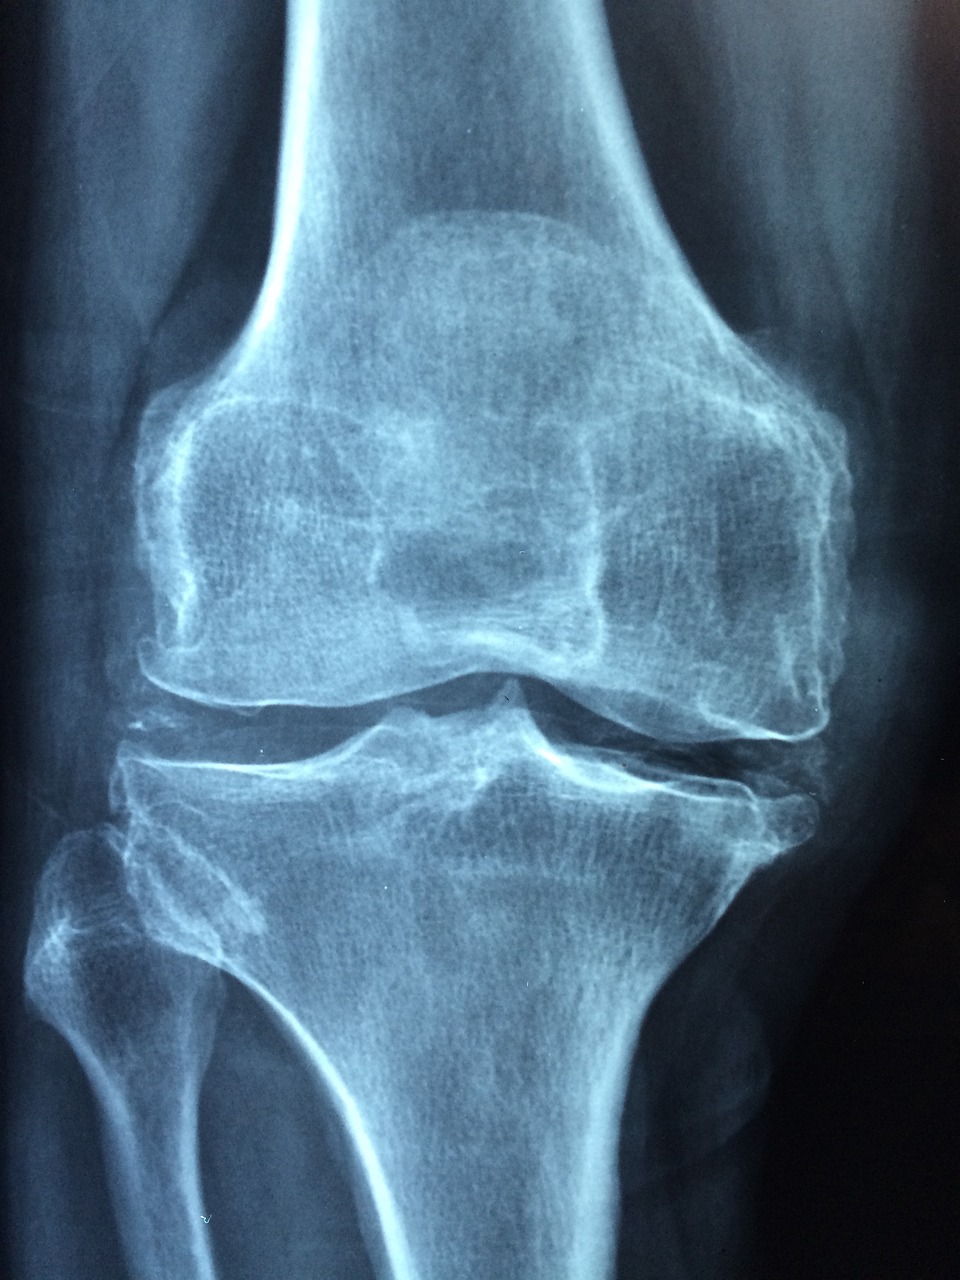

2. 골다공증 테스트 및 측정

골다공증을 진단하는 가장 일반적인 방법은 **이중 에너지 X선 흡수계(DXA)**를 이용하는 것입니다. 이 테스트는 골밀도를 측정하고 골다공증이 있는지 확인하기 위한 T-점수를 제공합니다.

2) 추가 테스트

- 정량적 초음파: 종종 발뒤꿈치에 적용되는 음파를 사용하여 골밀도를 측정하는 예비 검사 방법입니다.

- 뼈 회전율 지표: 뼈가 얼마나 빨리 분해되고 재건되는지 평가하고 치료 모니터링에 도움이 되는 혈액 검사입니다.